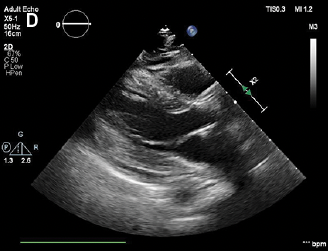

Delayed Pericardial Effusion Following Left Atrial Appendage Closure

“This is a very interesting analysis of 369 patients who underwent left atrial appendage closure at the Cleveland Medical Center,” comments Dr. Bhatt. “The authors compared patients who developed effusion to patients who did not to determine if there was any factor that might predispose them to developing acute or delayed pericardial effusion. It was, I think, very insightful given the large number of left atrial appendage closures that are starting to occur.”